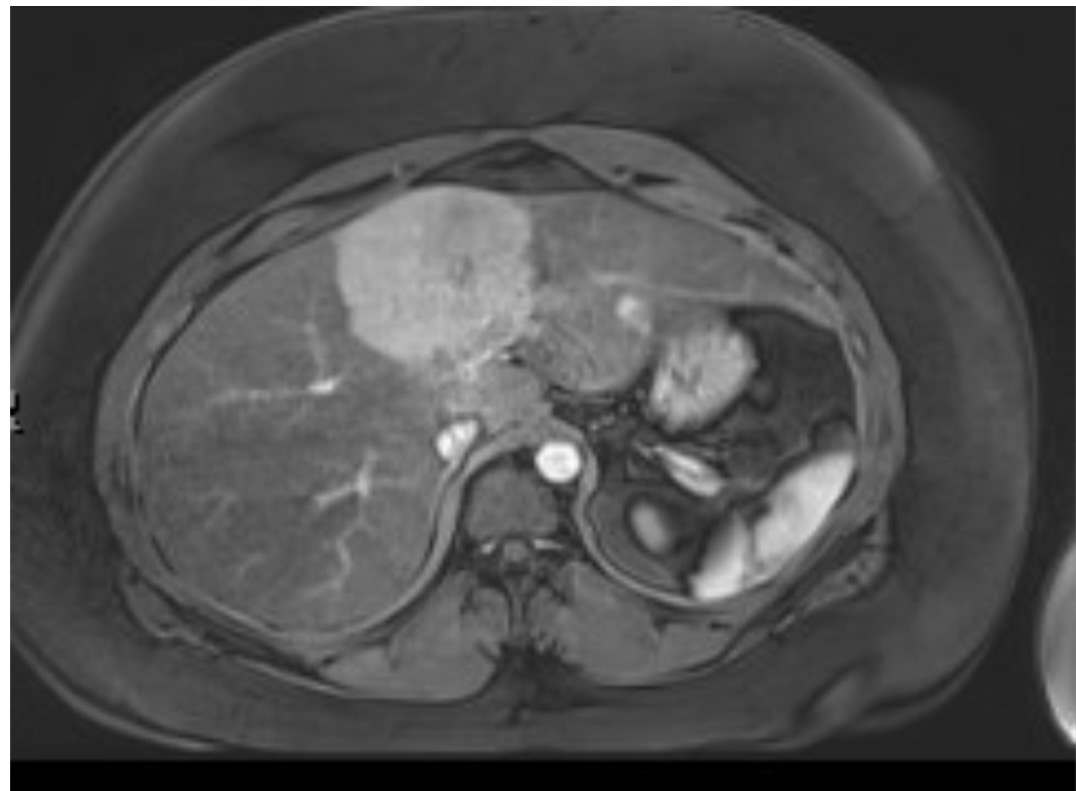

In October 2025, during one of those ER visits, doctors finally found something concrete: an 8 cm tumor in Megan’s liver, along with two smaller tumors and signs of severe non-alcoholic liver disease. Megan has no history of smoking, drinking, or chronic illness. She has always been healthy in both diet and lifestyle. The diagnosis was a shock—but it finally explained why her body had been failing her.